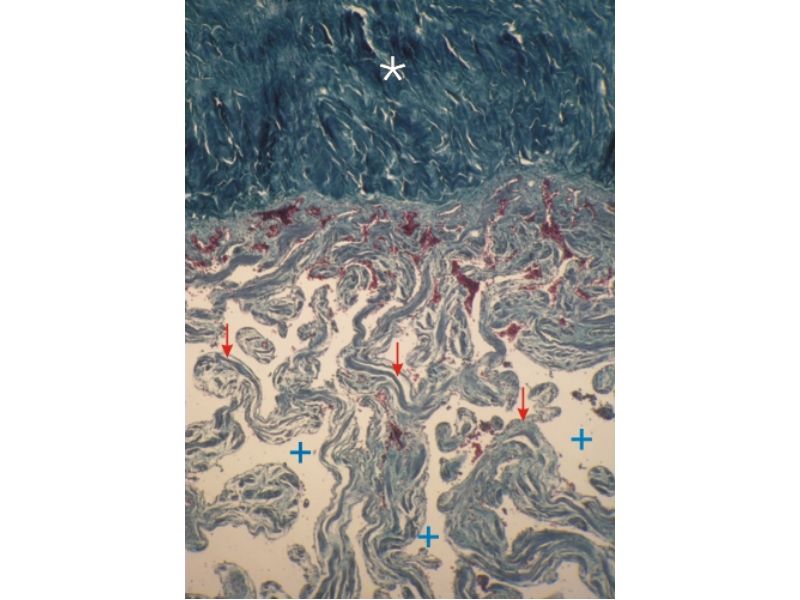

Penis

Slide 83Penis

- 3 cylindrical masses erectile tissue

- 2x corpora cavernosa

- 1x corpus spongiosum

- Surrounded by tunica albuginea

- Covered by skin

- Traversed by urethra

Tunica albuginea

- Fibrous connective tissue sheath

- Surround erectile bodies

- Dense collagen bundles

Corpora cavernosa

- Paired erectile bodies

- Irregular vascular spaces

- Lined with endothelium

- Trabeculae CT

- Smooth muscle cells

Corpus spongiosum

- Erectile body surrounding urethra

- More elastic fibres

- Few smooth muscle cells

- Vascular spaces uniform